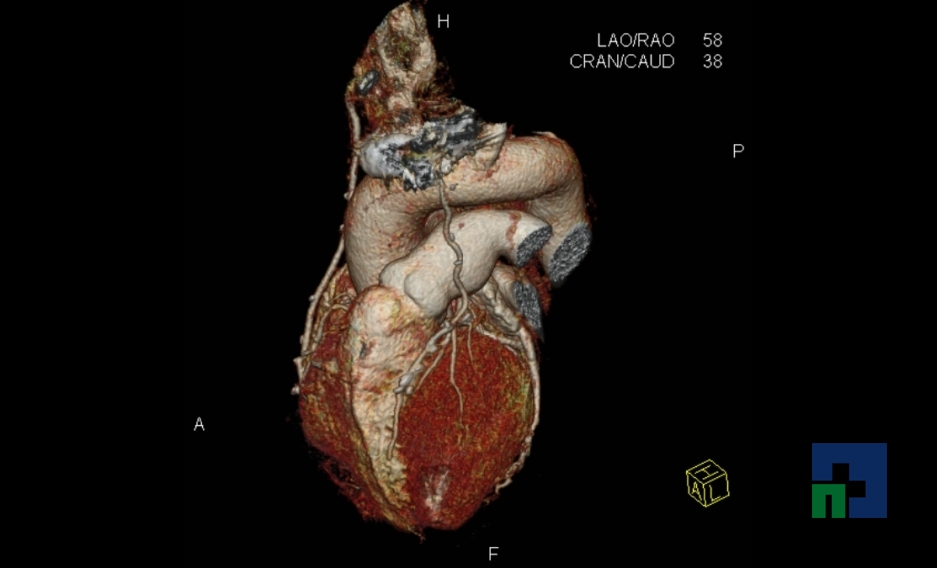

Examinare de rutină cerebrală, nativ și cu substanță de contrast (SDC) pentru diagnosticul:

- Accidentelor vasculare cerebrale ischemice sau hemoragice